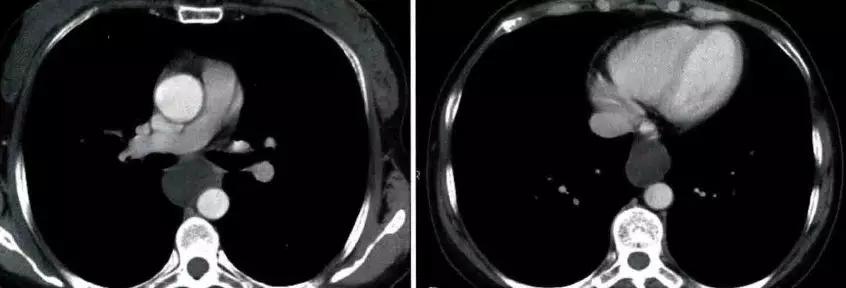

胸腺癌影像表现为前纵隔大的肿块,通常边界不清楚,边缘不规则或分叶状,常侵犯并推移邻近结构。常有坏死、出血和(或)囊性变,10% ~ 40%在CT上可见灶状钙化。常侵犯心包、胸膜并出现心包和胸腔积液

鉴别诊断 侵袭性胸腺瘤:胸腺癌的侵袭性较侵袭性胸腺瘤更为明显,当出现神经受累(如膈肌麻痹)或淋巴转移、血行转移等征象时,往往提示肿瘤为胸腺癌或其他恶性肿瘤而不是侵袭性胸腺瘤。胸腺鳞癌通常缺乏包膜及瘤内纤维分隔;当肿瘤较大且瘤内缺乏分隔或结节状结构时,则支持胸腺癌而不是侵袭性胸腺瘤的诊断